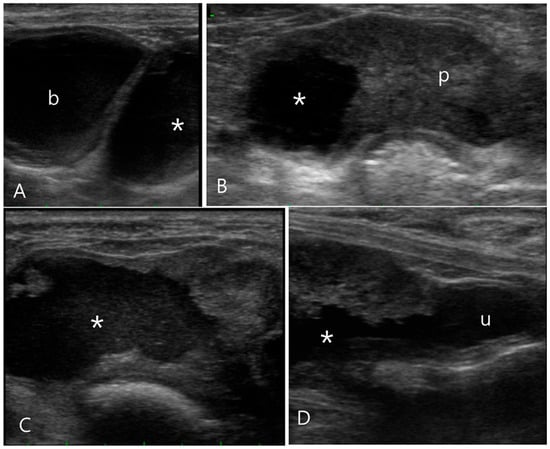

2.1. Case 1

2.2. Case 2

2.3. Case 3

2.4. Case 4

2.5. Case 5

2.6. Case 6